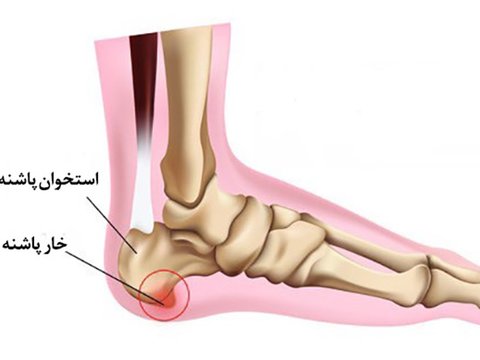

هنگام شروع آسیب درد بعداز مدتی التیام می یابد و فرد آسیب را تقریبا بعد از 6 هفته فراموش می کند .اما در محل پاشنه، بدن در جهت بهبود آسیب اقدام به رسوب کلسیم و سخت تر کردن محل اتصال لیگامان به پاشنه می کند.

در صورتی که کلسیمی شدن محل بارها و بارها اتفاق بیفتد ،علاوه براینکه درد دائمی تر می شود ، در بعضی موارد منجر به تشکیل زائده استخوانی در پاشنه موسوم به خار پاشنه می گردد.

ممکن است در عکس های رادیولوژی زائده استخوانی دیده نشود،اما داشتن درد در پاشنه به تنهایی هم می تواند هشدار خار پاشنه باشد.